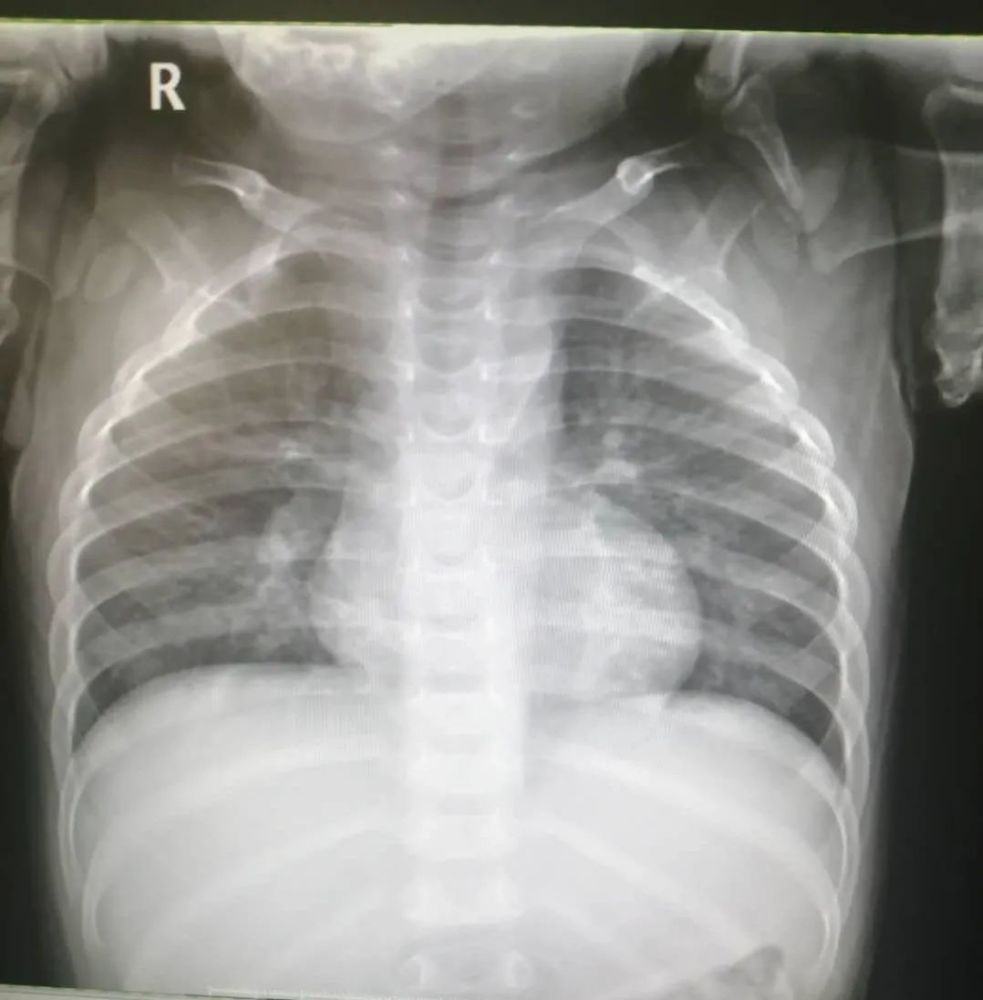

放射科数字dr胶片胸片正位异常片

门诊胸片如下图所示:患儿,男,1 岁 2 月,因「咳嗽 4 天发热 2 天」